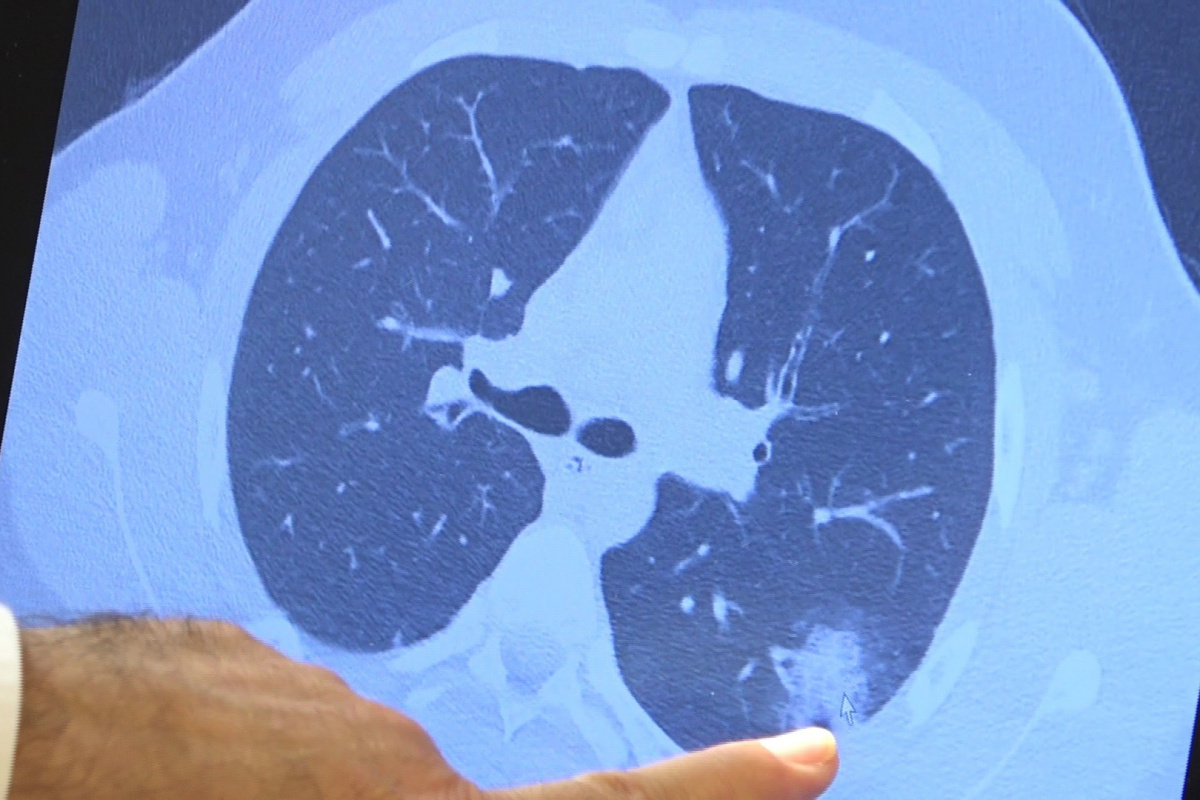

VM Medical Park Samsun Hastanesi Göğüs Hastalıkları Kliniği'nden Prof. Dr. Şevket Özkaya ise aşı olabilecek yaş grubundaki çocukların bir an önce aşılanması gerektiğine vurgu yaptı. 14 yaşında, kronik rahatsızlığı olan ve akciğerlerinde tahribattan dolayı ciddi öksürük, ateş ve nefes darlığı çeken bir hastanın akciğerlerini inceleyen Prof. Dr. Özkaya, "14 yaşındaki kronik rahatsızlığı mevcut olan bir genç hastamızda ciddi akciğer tutulumları var. Her iki akciğerinde de yaygın buzlu cam ve konsolidasyon alanları var. Bu yaştaki çocuklarda beklemediğimiz bir durumdur. Okullarımızda da bu risk var. Okullarımızın açık kalmasının ve sağlık sistemimizin kitlenmemesi için mutlaka aşı olmalıyız. Çocuklarımıza rol model olmalıyız. Şu anda hastanelerimiz hastalara yetişebiliyor. Yatak sayımız yeterli. Ancak kontrollü sosyal hayatımızı düzene sokmadıkça ve aşı olmadıkça, gelecekte hastanelerde yatak sayısı sıkıntısı çekebiliriz" dedi.